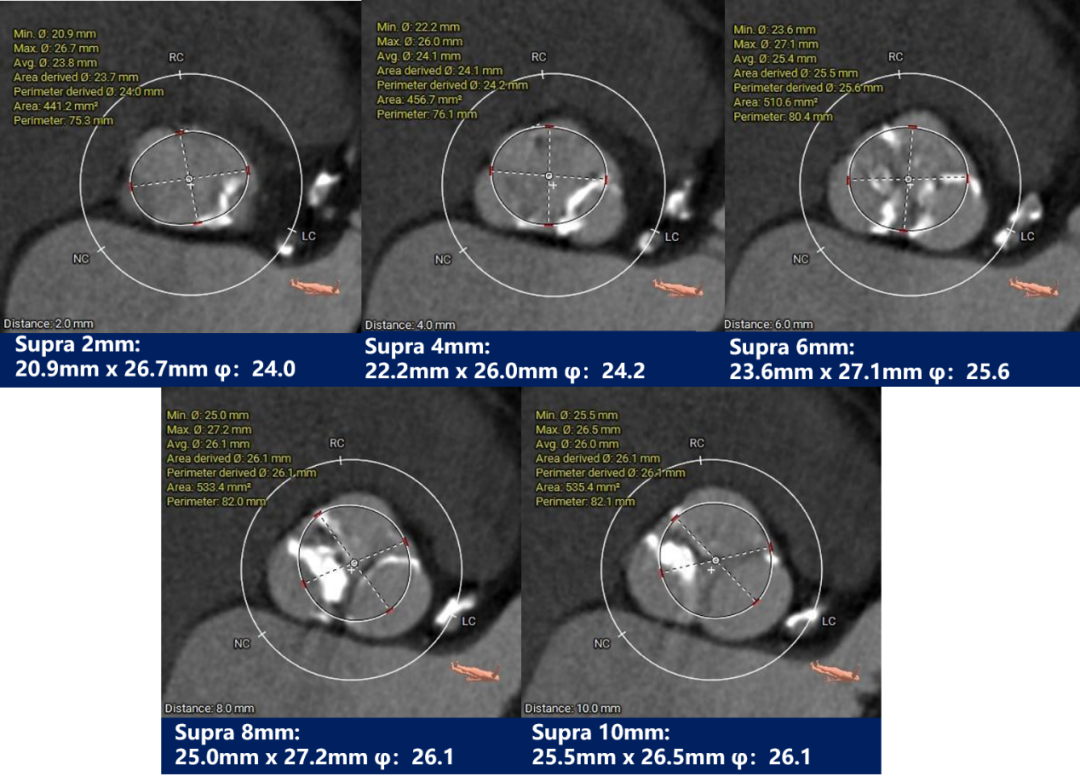

瓣上测量

因患者为三叶瓣且钙化基本分布在瓣叶上,决定不进行球囊预扩张;依据瓣环及瓣上测量结果,预装TaurusEliteAV26瓣膜,左右重合体位零位起始释放,结合正交体位进一步明确瓣膜植入深度,视情况决定是否后扩;